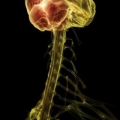

Воспаление спинного мозга. Вирусы и бактерии – одна из причин возникновения миелита, попадая в кровь, они могут попасть в спинной мозг и вызвать данное заболевание. Кроме того миелит могут вызывать различные токсические вещества.